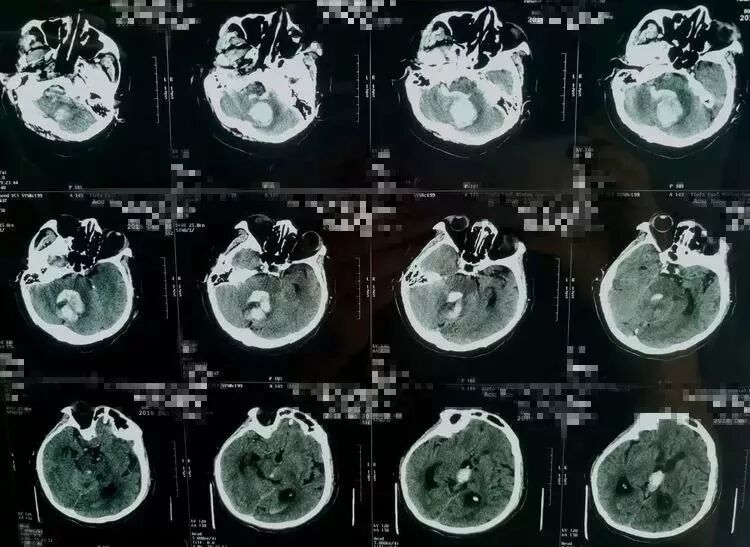

突发头痛,意识不清1小时。既往高血压病史多年,未系统治疗。自主呼吸深大,瞳孔正常大小。CT显示小脑蚓深部大量脑内血肿,IV脑室受压移位,III脑室及侧脑室内积血,左侧丘脑少量出血。

术后病人意识水平明显改善,刺激睁眼,双侧肢体自主活动。复查头CT显示小脑血肿清除满意,左侧丘脑内血肿未见增加,治疗中…

手术行枕下正中入路,应用锁孔通道技术,吸除脑内血肿,进一步清理IV脑室内积血,责任血管止血可靠,术毕。